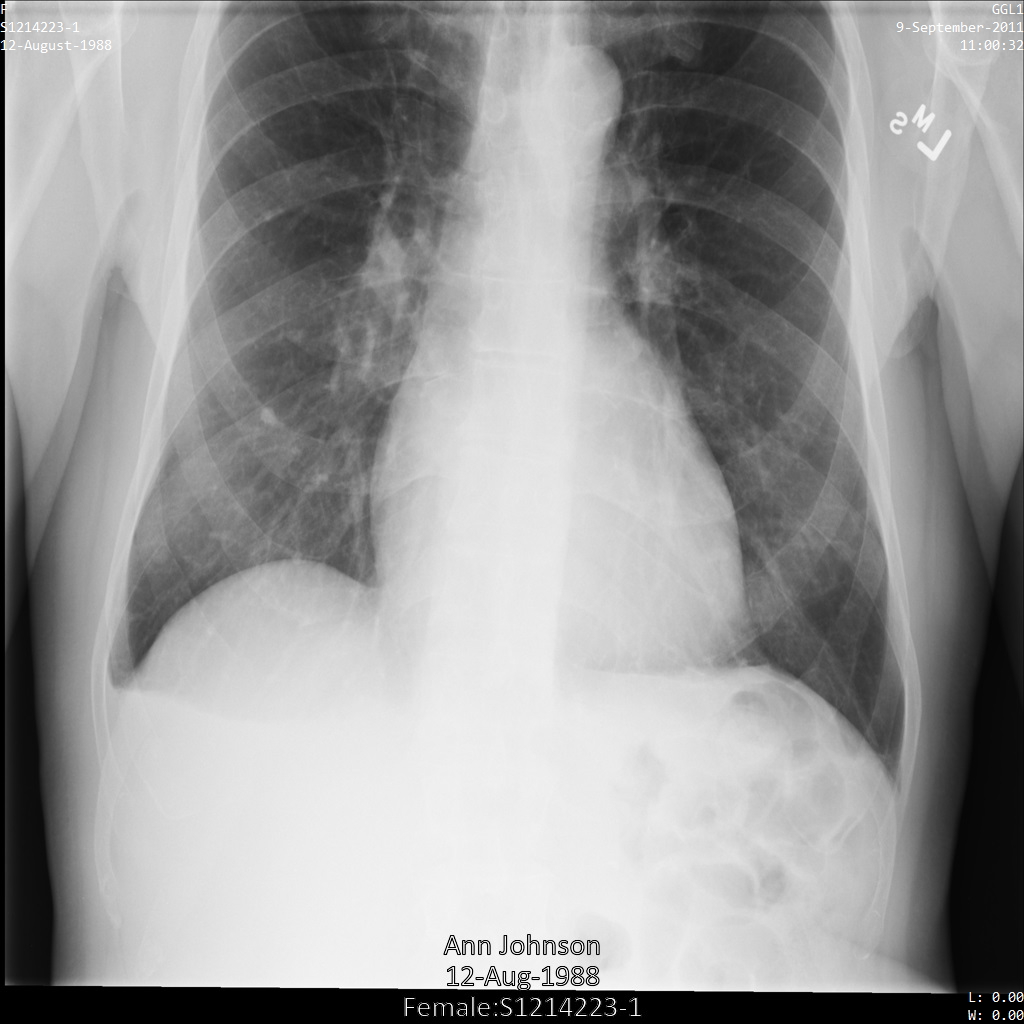

使用 ATTRIBUTE_CONFIDENTIALITY_BASIC_PROFILE 标记过滤条件配置文件将图片提交到 Cloud Healthcare API 后,图片显示如下。虽然图片顶部角落显示的元数据已被遮盖,但图片底部的烧屏 PHI 仍会保留。如需一并移除烧屏文字,请参阅遮盖图片中的烧屏文字

dicom_attribute_confidentiality_basic_profile